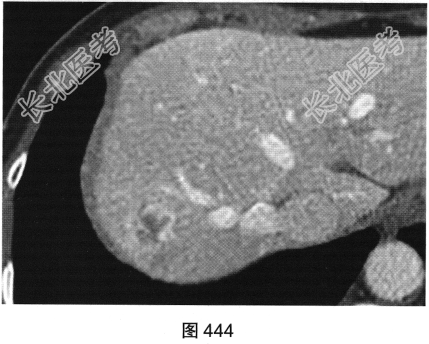

患者女性,53岁,体检经上腹部超声发现肝右叶一个稍高回声光团。查体:腹平软,右上腹无压痛,无反跳痛,肝脾肋下未及,Murphy征阴性,肝浊音界存在,肝上界位于右锁骨中线第五肋间,肝区无叩击痛,移动性浊音阴性。实验室检查:肝功能未见异常,AFP(—)。患者进一步行上腹部CT检查,如图442~图445所示。

- 多项选择题1.请问CT图像中可见哪些影像学发现( )

D、增强扫描动脉期病灶边缘结节状强化,强化程度与血管接近

F、增强扫描门脉期及延迟期强化范围向病变中心逐渐扩展